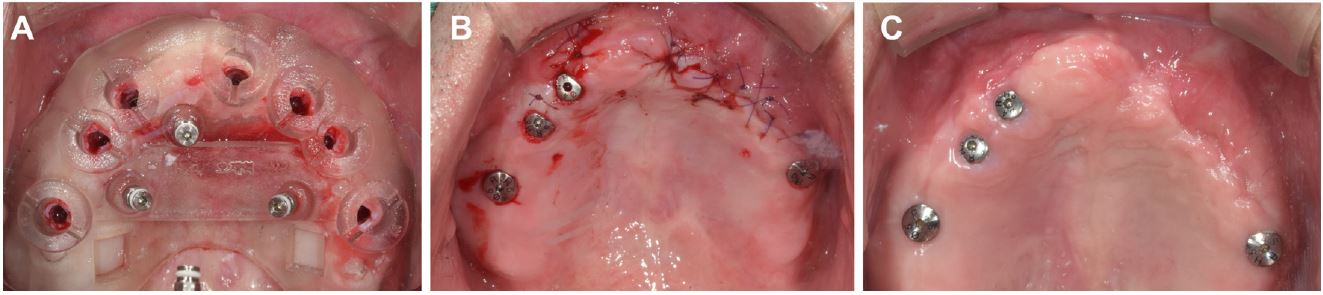

After 6 months, seven implants that were sandblasted with alumina and had acid-etched surfaces (TS III SA; OSSTEM, Seoul, Korea) were placed under local anesthesia via guided surgery (OneGuide Kit; OSSTEM). A surgical guide stent was designed in collaboration with a prosthodontist for the optimal prosthodontic requirements of the precise augmented bone region using a CBCT reference image and three-dimensional (3D) implant planning software.

Minimally invasive surgery was initially attempted using a commercial guide surgery kit (OneGuide Kit; OSSTEM) (Fig. 5A); however, xenogeneic bone (Bio-Oss; Geistlich Pharma AG) was grafted onto the inter-implant area between #21i and #23i and onto the coronal part of #23i and #24i because of the exposure of one to two threads of the implant fixture. For this additional procedure, only a horizontal incision was performed (Fig. 5B). All implant fixtures achieved primary stability, and healing abutments were connected, except for implants placed in grafted sites connected by cover screws (Fig. 5C). Table 1 shows the size of the implant and the information on the initial torque.

Fig. 5.

Clinical photographs for the implant placement. (A) Implant surgery using a surgical guide with three additional anchor screws for fixation, (B) Additional bone graft is performed only for the #21i, #23i, and #24i areas, and primary closure is performed, (C) One-month postoperative follow up.